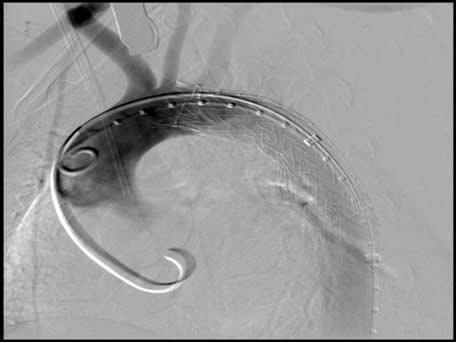

Figure 1: Digital subtraction imaging (DSA) with marker pigtail catheter in distal ascending aorta, guidewire advanced and curled around aortic valve and stent graft deployed covering left subclavian artery.

Fluoroscopy is the backbone for the workup, evaluation, and successful deployment of thoracic aortic stent grafts. Although fluoroscopic imaging for the preoperative work up of thoracic aortic pathology is often unnecessary with advanced CT and MRI imaging techniques, preoperative fluoroscopy may be necessary for the arteriography of the aorta and great vessels to determine precise anatomical relations when proximal landing zone (LZs) of the stent graft cannot be determined by non-invasive imaging. When using fluoroscopy for measurements, a marker catheter, with 1cm radiopaque markers, is useful to avoid parallax error (Figure 1). Parallax error is the difference is length measurements that occur when the C-arm is moved toward or away from the patient and the relative relationships of landmarks and lesions are altered.